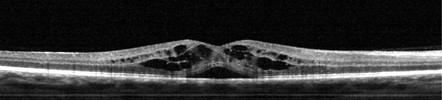

Eye Wellness Exam Examples

Healthy Retina Unhealthy Retina

Diabetic Retinopathy

Macular Degeneration

Glaucoma